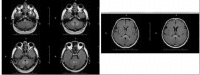

Figure 2

After 17 days, axial fluid-attenuated inversion recovery (FLAIR) images show normal signal intensity in the medulla oblongata, pons, mesencephalon and dentate nuclei but increased signal intensity in the cerebral peduncles. Increased signal intensity in the splenium of the corpus callosum is continued